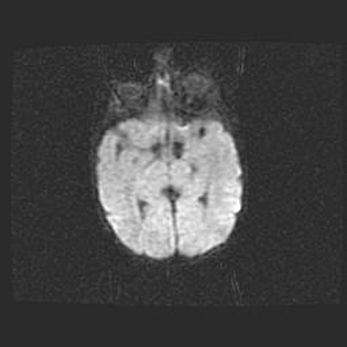

Множественные кисты обоих полушарий головного мозга, наибольшая из них в правой затылочной области. Ассиметричная атрофическая гидроцефалия.

Возраст: 7 месяцев

Вес: 5660 г

Пол: мужской

Окружность головы: 41,5 см

Срок гестации: 28-29 недель

Кисты головного мозга развиваются в результате многоочаговых некрозов вещества мозга и возникают вследствие перенесенной перинатальной инфекции, менингитов, энцефалитов, асфиксии, родовой травмы, расстройств мозгового кровообращения различного генеза. Образованию кист в веществе головного мозга плодов и новорожденных способствуют такие факторы, как высокое содержание в нем воды, недостаточная (или отсутствие) миелинизация и слабая астроглиальная реакция на повреждение.

Кисты могут сочетаться с гидроцефалией и другими поражениями головного мозга.